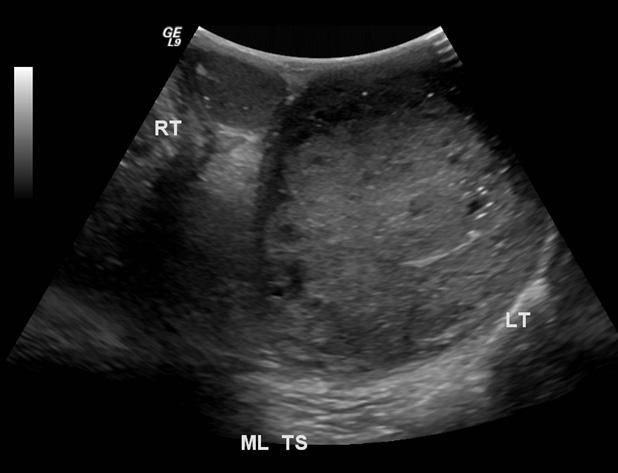

Медицина и диагностика: Инвазивный пузырный занос на УЗИ

Раздел: Альбом идей